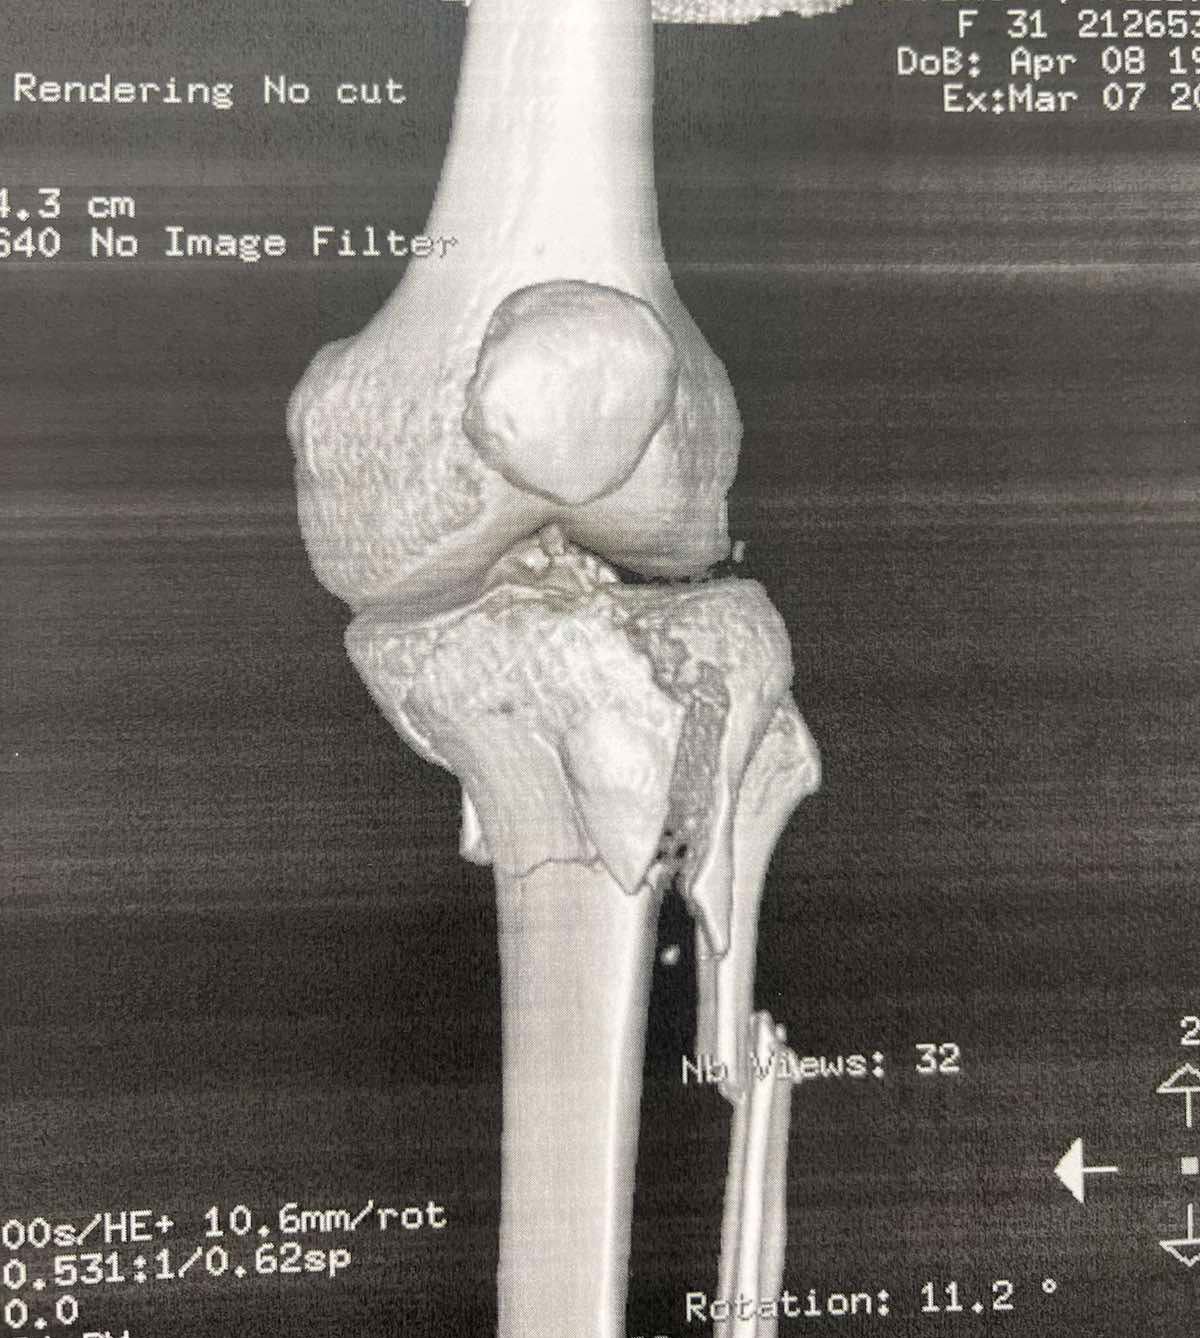

Πριν το χειρουργείο (απεικονίσεις τραυματισμού)

Τα κατάγματα του κνημιαίου πλατώ αφορούν την άνω επιφάνεια της κνήμης που συμμετέχει στην άρθρωση του γόνατος. Η ταξινόμηση Schatzker χρησιμοποιείται ευρέως για να περιγράψει το μοτίβο του κατάγματος.

Ο Schatzker τύπος VI είναι από τις πιο βαριές κακώσεις: πρόκειται για κάταγμα του πλατώ με μεταφυσιο-διαφυσιακή ασυνέχεια(δηλαδή «διαχωρισμό» της μεταφύσεως από τη διάφυση), συχνά μετά από υψηλής ενέργειας τραυματισμό. Τέτοιες κακώσεις μπορεί να συνοδεύονται από σημαντικό οίδημα/βλάβες μαλακών μορίων και απαιτούν ιδιαίτερη προσοχή στον χρόνο και στον τρόπο αποκατάστασης.